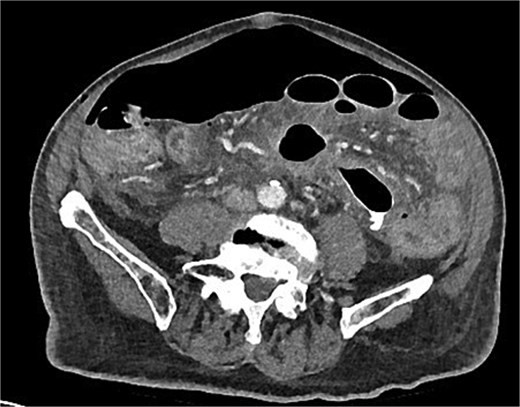

A chest x-ray confirmed new right lower lobe consolidation and demonstrated interval development of massive pneumoperitoneum compared to the CT scan 3 days prior (Fig. 2). A repeat CT scan was therefore undertaken, revealing large volume pneumoperitoneum with free gas locules but no rectal contrast extravasation at the region of the anastomosis (Fig. 3).

Day 10 CT scan demonstrates ileus with large volume pneumoperitoneum with free air around anastomosis.